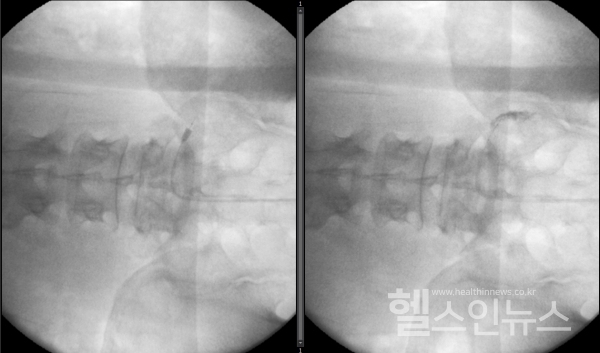

풍선확장술은 끝에 작은 풍선이 달린 가느다란 관을 꼬리뼈 부위로 삽입하여 신경관이 좁아진 부위를 미세하게 넓혀 약물을 투여할 수 있다. 따라서 일반적인 신경성형술을 통한 유착박리 보다 좀 더 나은 효과를 기대해볼 수 있다. 시술 2~3개월 이후에도 증상이 호전되지 않거나 효과가 일시적인 경우 질환이 많이 진행하여 질환이 고착화 된 것으로 판단한다. 이 경우에는 비수술적 치료로는 더 이상의 효과를 기대하는 데 한계가 있으므로 수술적 치료를 고려하게 된다.

강동경희대학교병원제공,오른쪽5번요추신경공에카테터를진입시킨후풍선을확장한영상(왼쪽),이후신경공에약물을주입한영상(오른쪽).